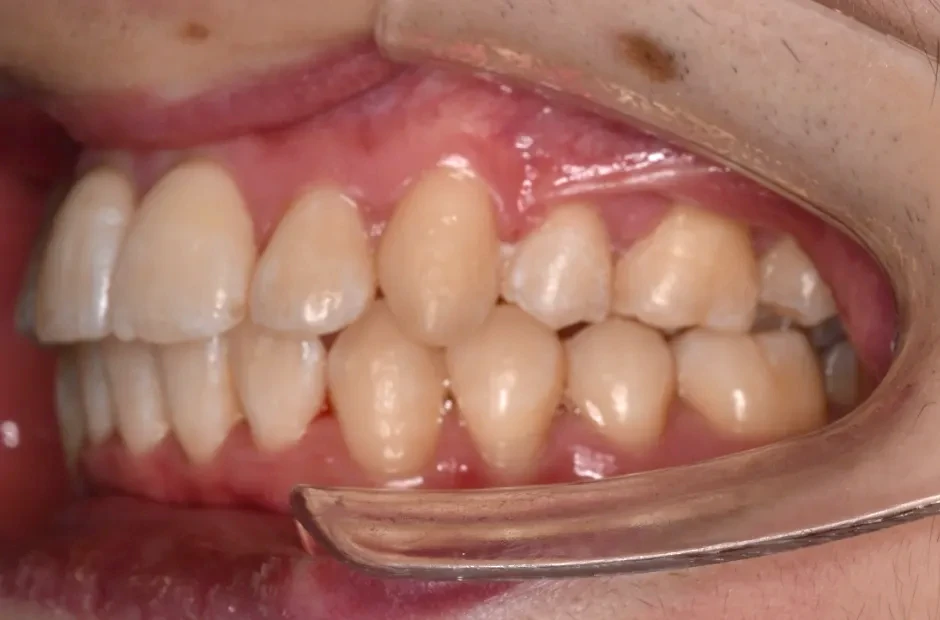

治療症例

ブラケット矯正

前歯部反対咬合

| 診断名・主訴 | 前歯部反対咬合 |

|---|---|

| 年齢・性別 | 14歳・男性 |

| 治療期間・回数 | 1年2か月 |

| 治療に用いた主な装置 | ブラケット矯正 |

| 抜歯部位 | なし |

| 治療費 | 60万円(税抜) |

| リスク・副作用 | 装置による違和感・疼痛・歯肉退縮・歯根吸収・虫歯のリスクなど |

治療後